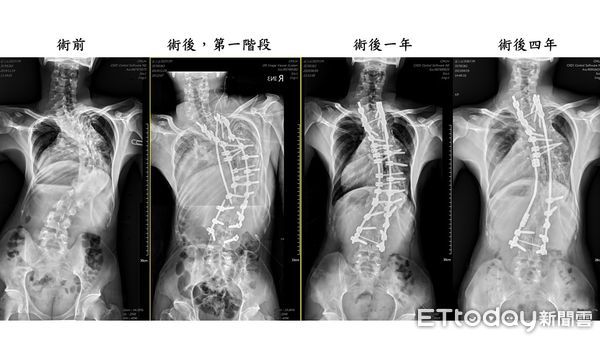

▲緬甸「龜背少年」番玉磊成功手術後每年定期追蹤,均維持良好狀態。(圖/記者蔡佩旻翻攝)

脊椎中心陳賢德陳賢德主任表示,「龜背少年」為駝背且脊椎嚴重側彎的病症,已壓迫到肺臟、心臟功能,影響生命安全。手術採用「3D導航輔助脊椎畸形截骨矯正手術」,單是第一次的手術就從早上7點到隔日凌晨3點,馬拉松式過程,終在團隊合作下順利完成手術。